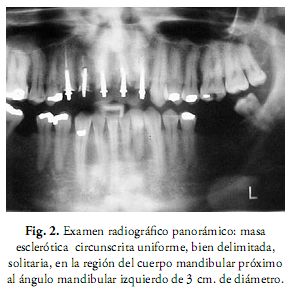

El examen radiográfico panorámico reveló una masa esclerótica circunscrita uniforme, bien delimitada, solitaria, en la región del cuerpo mandibular próximo al ángulo mandibular de aproximadamente tres centímetros de diámetro (Fig. 2).

Las radiografías tradicionales y tomografías computarizadas muestran a los osteomas como masas radiopacas, con formato ovalado, bien definidas y circunscritas, unidas por una amplia base o pedículo implantado hacia la cortical ósea (1, 2, 7-9). Los exámenes radiográficos de rutina generalmente son suficientes para el diagnóstico de osteoma, observándose como radiopacidades bien delimitadas, densas, similares al hueso normal. La radiografía panorámica, la de Waters o la tomografía computarizada muestran hallazgos compatibles con la naturaleza benigna y establecen con claridad la posición de la lesión. El uso de la tomografía revela la ausencia de afectación de otras estructuras, delimita y localiza exactamente el daño, lo que puede resultar determinante en el diagnóstico final del tipo de lesión (6, 8, 17).